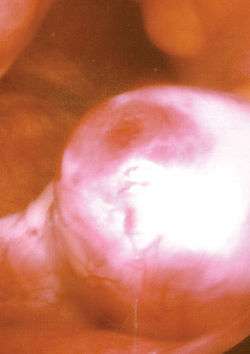

The moment of ovulation has been photographed.[19]